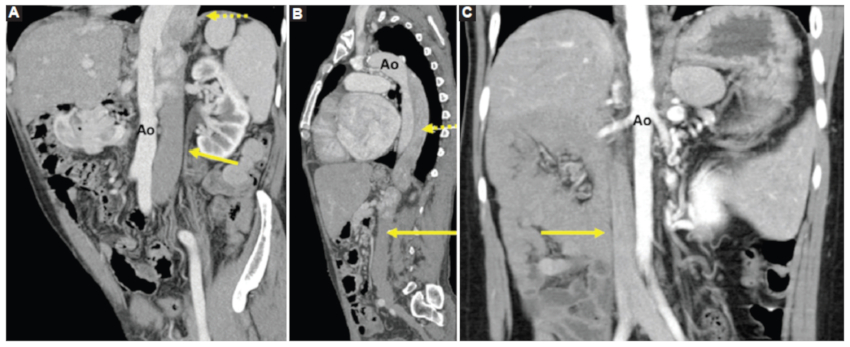

Otras anomalías que se pueden encontrar son la vena porta preduodenal, que puede interferir en el desarrollo normal del páncreas, como en el caso 4 (Fig. 10) (2.

Páncreas

Las anomalías del páncreas son frecuentes y bien conocidas. El hallazgo más frecuente es el de un páncreas trunco, con presencia de la cabeza pancreática y una pequeña parte del cuerpo como se vio en los casos 1, 3 y 4 (Fig. 11). Las anomalías del páncreas y bazo se asocian, debido al desarrollo embrionario común14.

Bazo

La mayoría de los casos de síndrome de heterotaxia con isomerismo izquierdo se asocia a la existencia de múltiples bazos, de distinto tamaño pudiéndose encontrar en cualquier localización, pero más frecuentemente próximos a la curvatura mayor del estómago, como en los casos 1, 3 y 4 (Figs. 11 y 13). Esta estrecha relación está determinada por el desarrollo embriológico14.